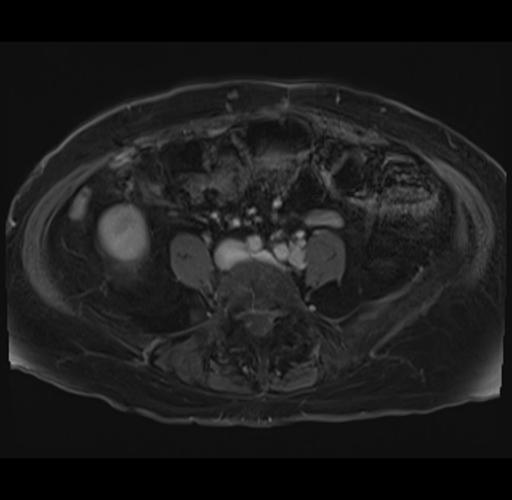

Axial Venous

MRI T1